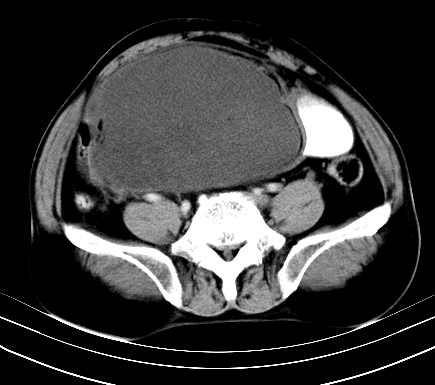

标题: CT19729B:男,74岁,因腿疼就诊,查体触腹部肿物,

增强扫描

静脉期

【ct表现】

1、肿块巨大,往往位于腹膜后,长大后才引起症状而就诊;那么位于腹膜后的肿瘤80%为恶性肿瘤。

2、实性肿瘤,增强扫描轻度不均强化,实性肿瘤一般不是好东西。

3、肿瘤边缘似见少许脂肪样密度。

4、腹膜后未见肿大淋巴结,但肿瘤于临近的肠管及组织接触紧密。

【诊断】

腹部占位,考虑位于腹膜后的恶性肿瘤,脂肪肉瘤(实体型)可能性大。

术后病理结果:腹膜后脂肪肉瘤。